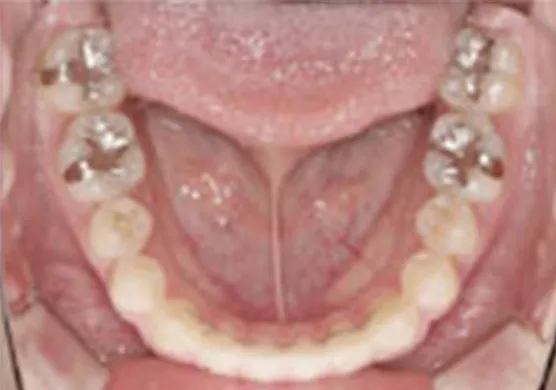

全体矯正・1期治療後の全体矯正

(2期治療)全ての歯に矯正装置を付けて、機能的・審美的要素を考慮して矯正治療を行ないます。精密に歯並びを整えるため1本1本の歯を移動し、噛み合わせを改善するのが目的です。